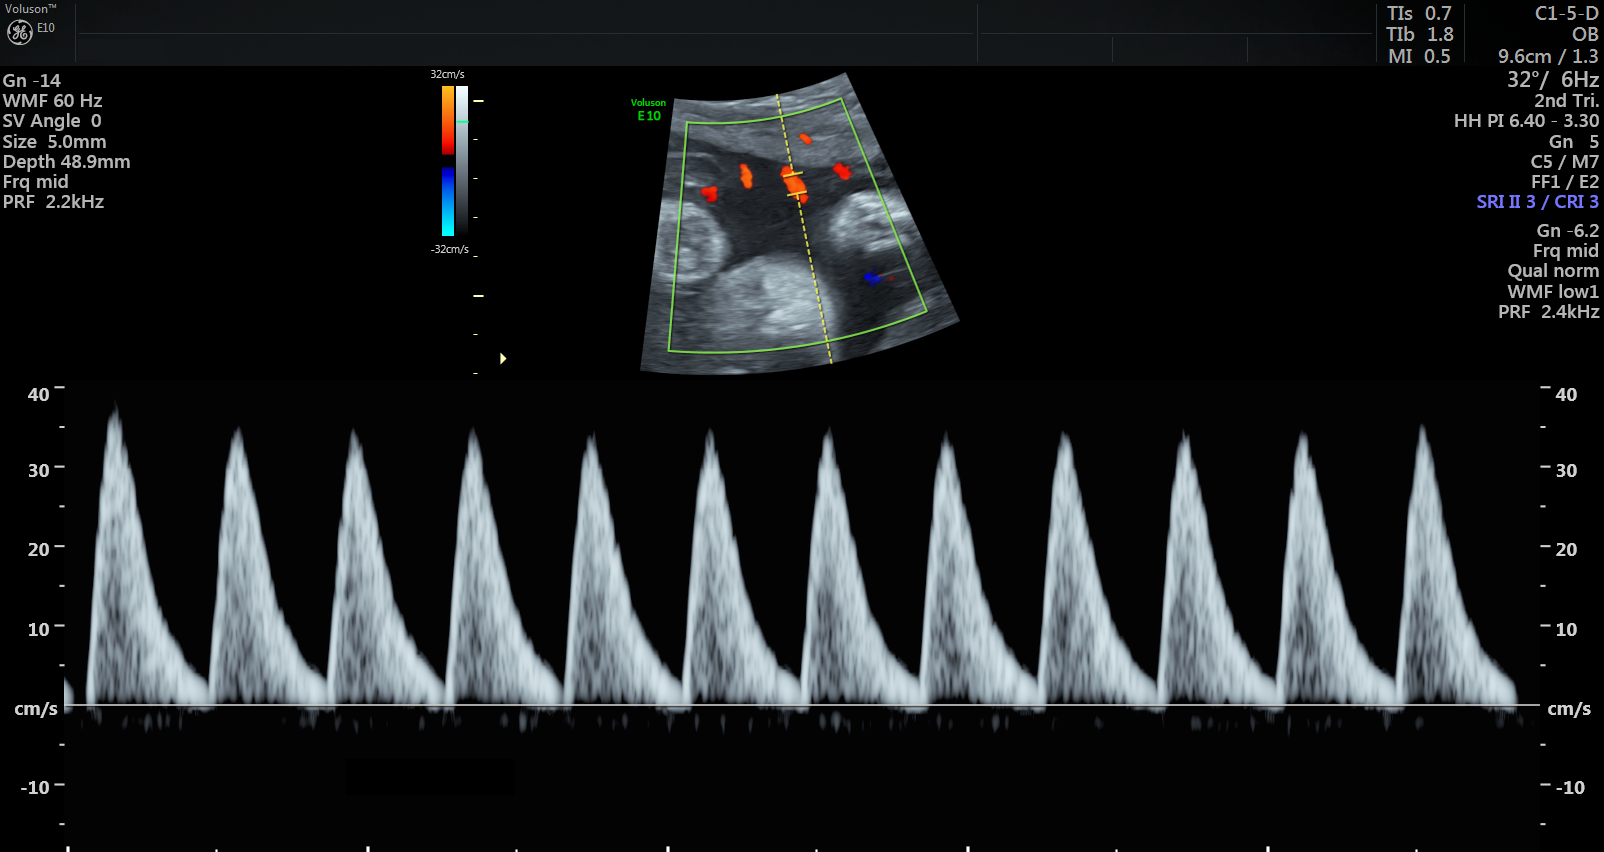

Currently, standard-of-care ultrasound scans measure blood flow at one point in the umbilical cord. The technique developed by Sled and his collaborators takes two measurements – one at the fetal end of the umbilical cord and one at the placental end. Sled says recording both measurements gives a much more accurate picture of the way blood is travelling through the umbilical cord.

“By looking at both measurements and the physics of how blood travels, we can get insight into how some of the finest blood vessels in the placenta are organized. The information this can provide to physicians is invaluable,” says Sled, who is also the Director of the Mouse Imaging Centre and a Professor and Vice-Chair in the Department of Medical Biophysics at the University of Toronto.